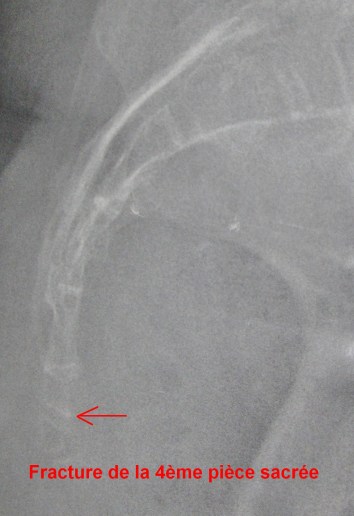

Souvenez-vous en avril 2017, en pleine répétition de théâtre, mauvaise chute sur le dos ! Je l’ai raconté dans cet article.

Double fracture de la 4ème vertèbre sacrée